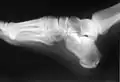

Raio-X de uma fratura de calcâneo